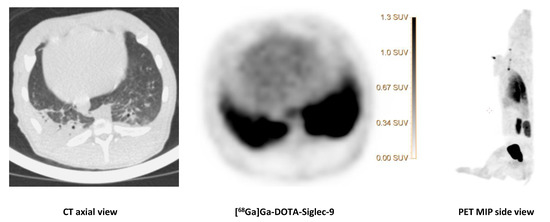

2.5. [68Ga]Ga-DOTA-Siglec-9

We saw no tracer activity neither in the early nor the late images of [68Ga]Ga-DOTA-Siglec-9 in 19 osteomyelitis lesions (Figure 6). Instead, the tracer accumulated in dorsocaudal parts of both lungs of, for example, pig 1 (Figure 7). The CT image showed signs of infectious foci in dorsocaudal parts of both lungs. We noticed, however, a general tendency of [68Ga]Ga-DOTA-Siglec-9 accumulation in the dorsocaudal parts of the lungs. We also observed this in pigs that did not develop OM or pulmonary infections (data not shown). Figure 8 demonstrates in images acquired 10 to 30 min after tracer injection, a marked 68Ga]Ga-DOTA-Siglec-9 uptake in the margin of an inguinal abscess adjacent to the S. aureus inoculation site. In the static images acquired after 60 min, the activity of [68Ga]Ga-DOTA-Siglec-9 decreased. Whereas the activity of [18F]FDG increased slightly in the margin of the abscess (Figure 8).

[18F]FDG and [68Ga]Ga-DOTA-Siglec-9] (early and late acquisition; 1 and 2 h) uptake in osteomyelitis lesion in the right medial condyle of the right distal femur (indicated by an arrow) of pig 1 and the corresponding CT (axial view). Comparable SUV scales are shown to the right of the PET images.

Figure 6. [68Ga]Ga-DOTA-Siglec-9 compared to [18F]FDG].

Molecules 25 04329 g006